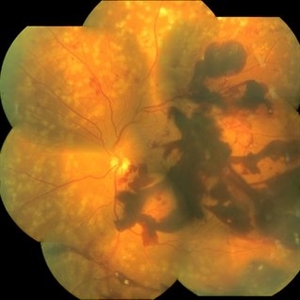

Bilateral Retinal Vaso-Occlusive Disease

35-year-old woman with bilateral retinal vaso-occlusive disease with secondary neovascularization. She has undergone extensive care including photocoagulation to both the retina. There is severe ischemia on the posterior pole in both eyes. Patient has been started on immunosuppressant.

Photographer: Ms . Ashwini Borde

Imaging device: zeiss plus IR 450

Condition/keywords: neovascularization (NV), vaso-occlusive disease